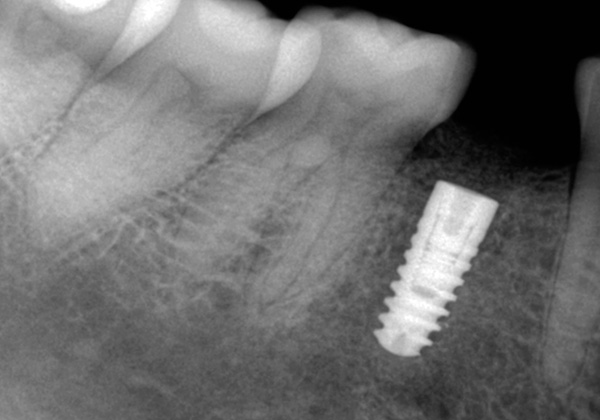

O fato de a gengiva durante o implante “não cirúrgico” sofrer lesões mínimas não exclui a necessidade de perfurar o osso da mandíbula usando um conjunto consistente de fresas. Afinal, a perna do implante é uma espécie de parafuso de titânio que você precisa literalmente parafusar no orifício.

Consequentemente, após realizar uma incisão circular com um mucótomo e remover o círculo gengival excisado, segue-se um estágio completamente padrão de preparação do orifício para a colocação do implante - expansão e aprofundamento dos cortadores.

- O furo se expande para o diâmetro desejado e se aprofunda;

- Em seguida, segue a instalação do implante e controla a profundidade de sua introdução;